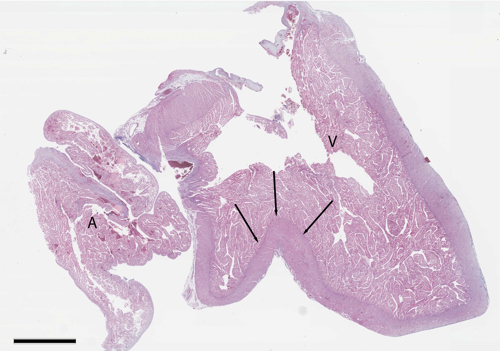

"Hjertepigg" (Link: Artikkel i National Library of Medicine) er et anatomisk fenomen som stadig ofteres påvises ved histopatologisk undersøkelse av yngel fra oppdrettlaks. Denne piggformede bruskstrukturen, som ligger ventralt for perikardialhulen, antas å kunne ha betydelige konsekvenser for hjertefunksjonen.

Hjertepiggen kan presse på hjertet og føre til innbuktninger i hjerteveggen. Bruskstrukturen varierer i størrelse og grad av innvirkning på hjertets morfologi. Noen ganger fører det til mildere innbuktning i ventrikkelveggen, mens andre ganger kan man se en kløft på ventrikkelens ventralside.

Hos større laks ser man ofte en fortykkelse av den kompakte hjertemuskulaturen ventralt i hjertet, og av og til betennelse i hjertets ytre hinne i det samme området. Disse forandringene kan være et resultat av den mekaniske irritasjonen forårsaket av bruskstrukturen. Årsaksforholdene rundt hjertepiggen er ikke fullt ut forstått, men en teori er at det kan skyldes ubalanse i veksten mellom hjertevevet og gjelleskjelettet.

Bilde: Mikroskopibilde av hjerte som viser en dyp innbuktning (piler) på ventralsiden av ventrikkelen. A= atrium, V= ventrikkel.